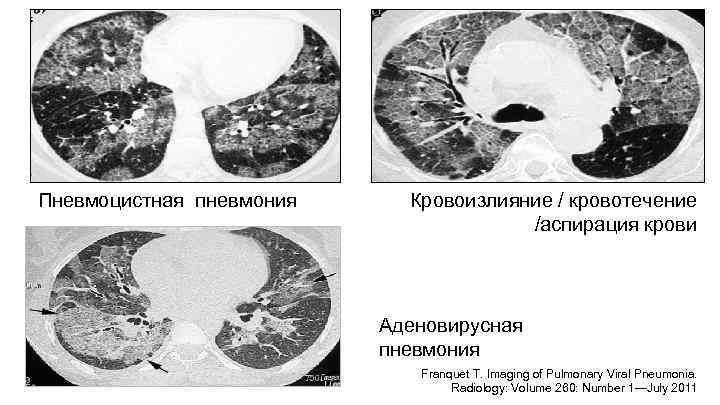

Пневмоцистная пневмония Кровоизлияние / кровотечение /аспирация крови Аденовирусная пневмония Franquet T. Imaging of Pulmonary Viral Pneumonia. Radiology: Volume 260: Number 1—July 2011

«Матовое стекло» как признак пневмонии Трудности диагностики: • Часто нет убедительных физикальных симптомов • Рентгенография: – изменения могут отсутствовать – «усиление легочного рисунка» – диффузное матовое стекло и/или консолидация • Выявление: КТ >>> рентгенография – В определенных клинических ситуациях КТ может быть методом выбора (напр. : лихорадка + иммунодефицит)